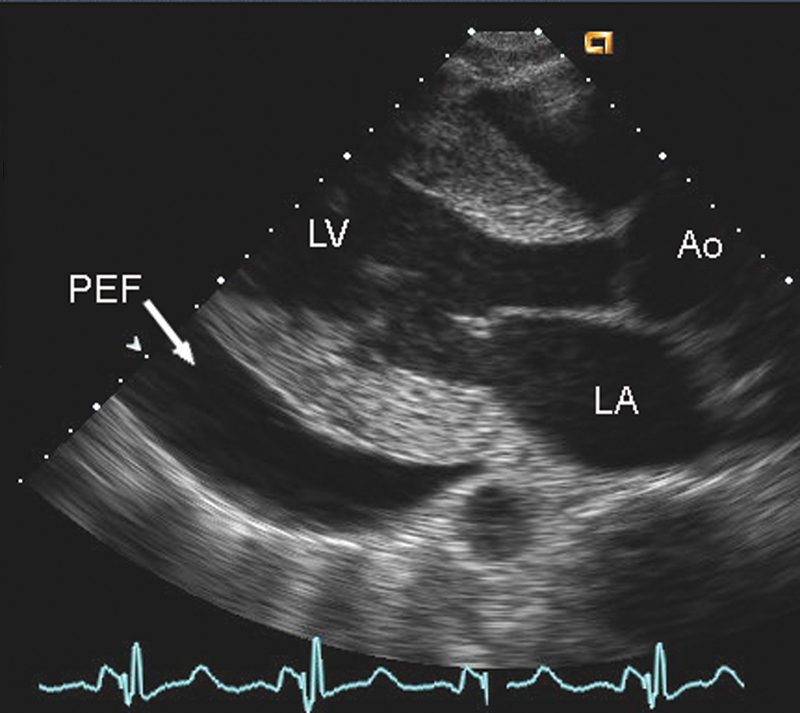

فحوصات تشخيصية لبعض امراض القلب والشرايين التاجية